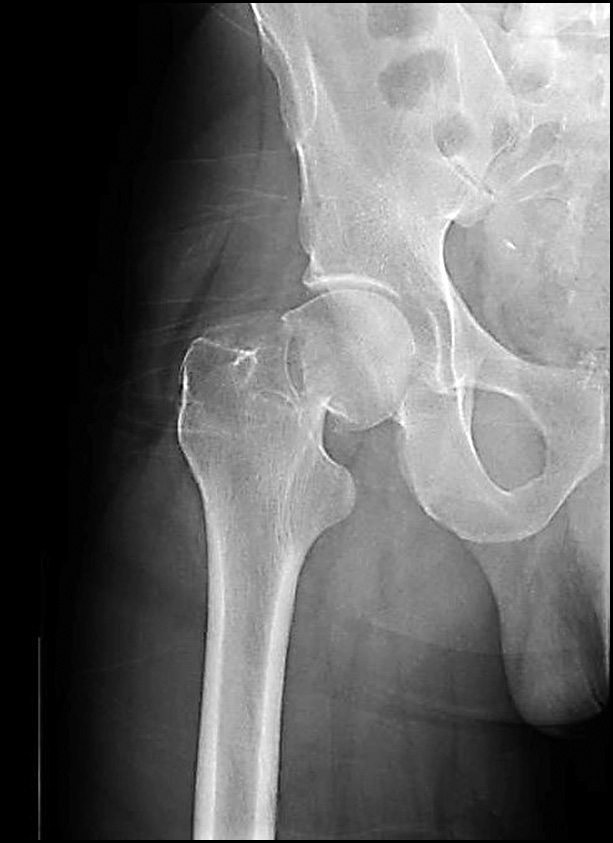

Следующий клинический пример демонстрирует достаточно редкий вид послеоперационного осложнения для группы исследования — миграцию металлофиксатора. Пациентка Н., № и/б 7124/2019, 50 лет, поступила в клинику через 1,5 часа после дорожно-транспортного происшествия с изолированным переломом ШБК справа, тип Garden III (рис. 5).

Рис. 5. Рентгенография тазобедренного сустава пациентки Н. при поступлении.

Fig. 5. X-ray of the hip joint of patient N. upon admission.

Учитывая возраст пациентки (50 лет), от эндопротезирования ТБС было решено воздержаться. Через 18 часов с момента получения травмы была выполнена операция методом ДДФ с использованием 4 телескопических винтов в ШБК (рис. 6).